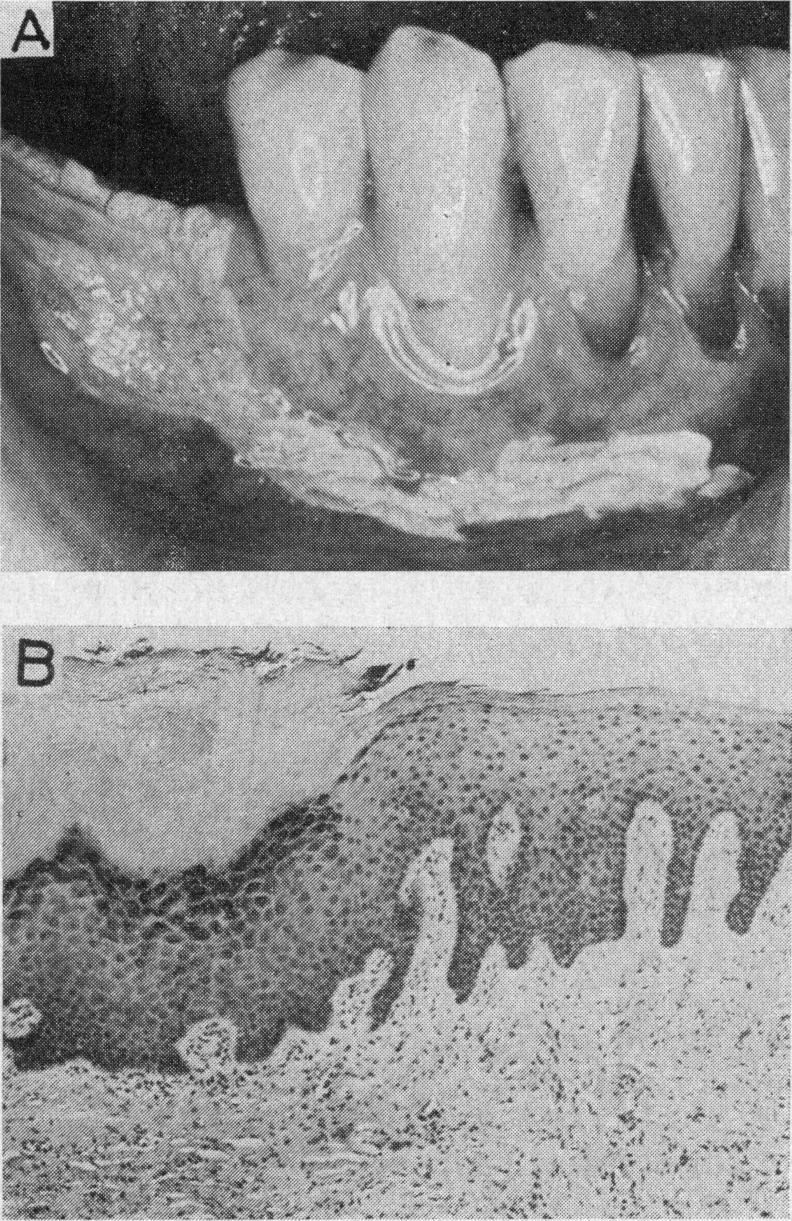

Leukoplakia buccalis: an enigma.

Proc R Soc Med. 1975 Jun;68(6):337-41. doi: 10.1177/003591577506800601.